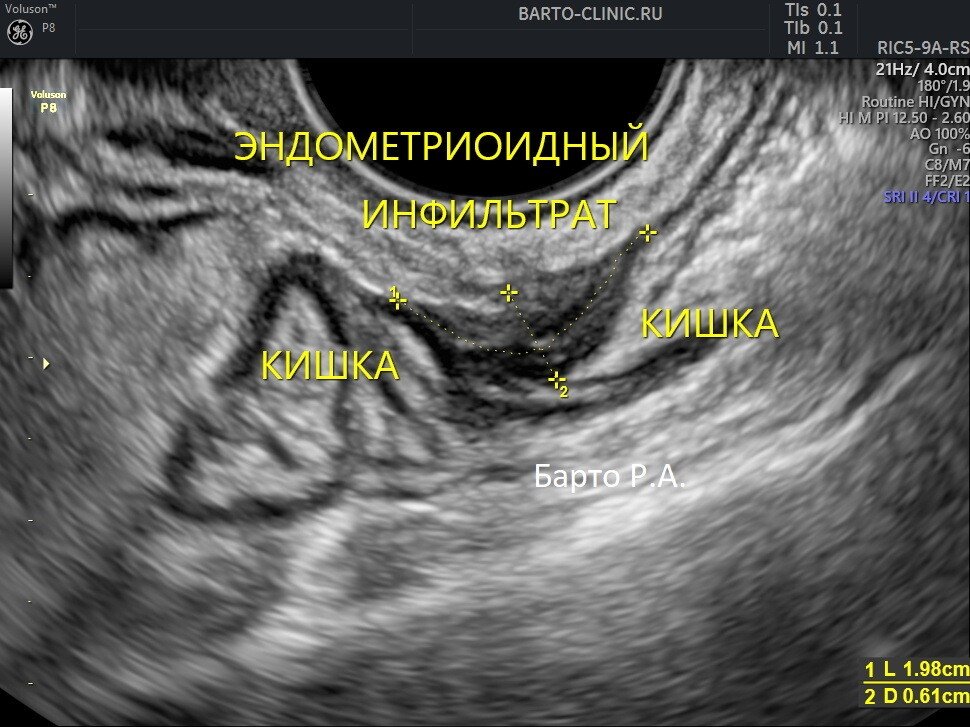

Узи покажет эндометриоз

Узи покажет эндометриоз 110 фото